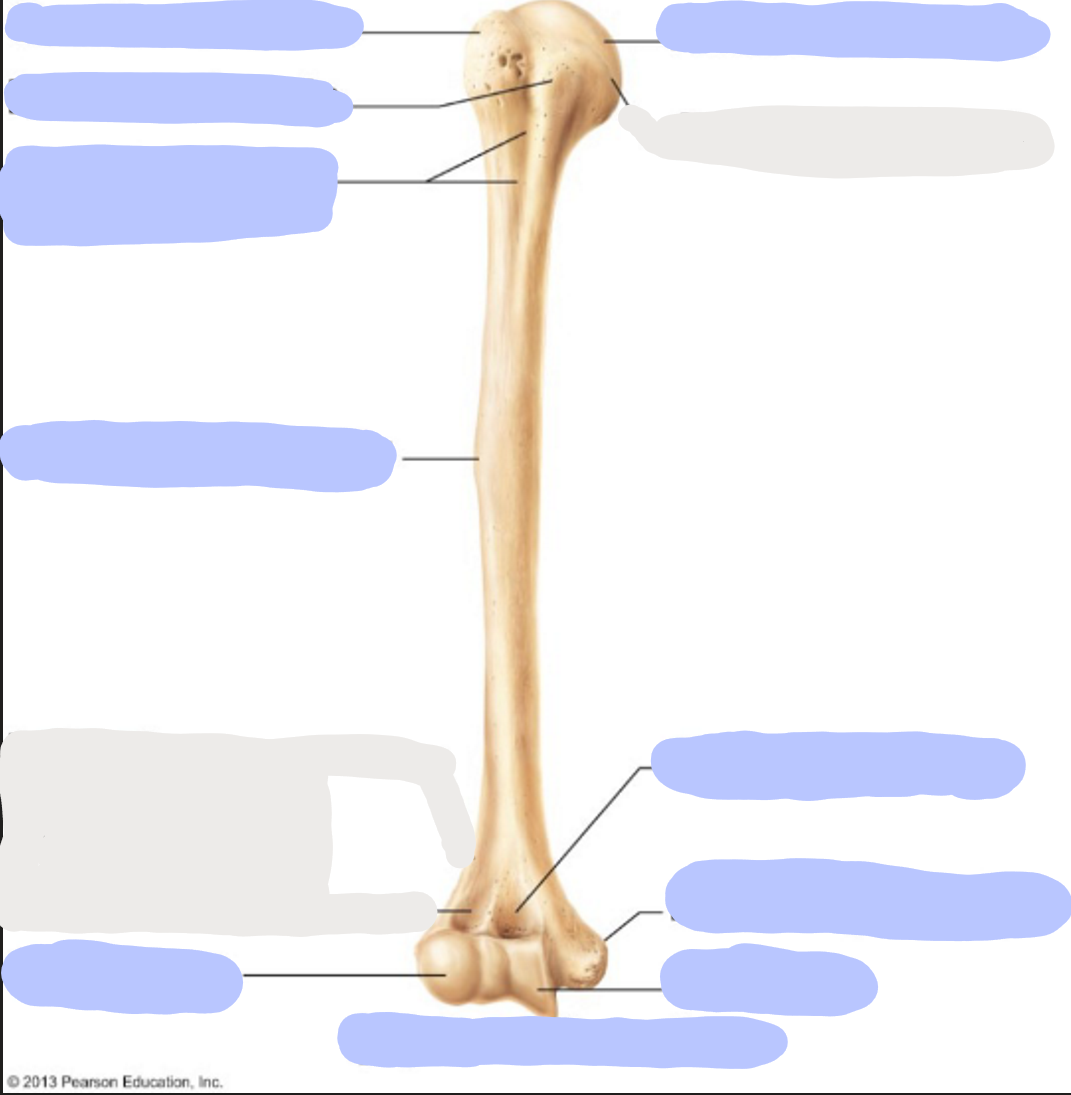

What is this picture of?

Anterior view of the Right Femur

What is here?

Where is the Neck of the Femur?

What is here?

Where is the Head of the Femur?

What is here?

Where is the Lesser Trochanter of the Femur?

What is here?

Where is the Lateral Epicondyle of the Femur?

What is here?

Where is the Medial Epicondyle of the Femur?